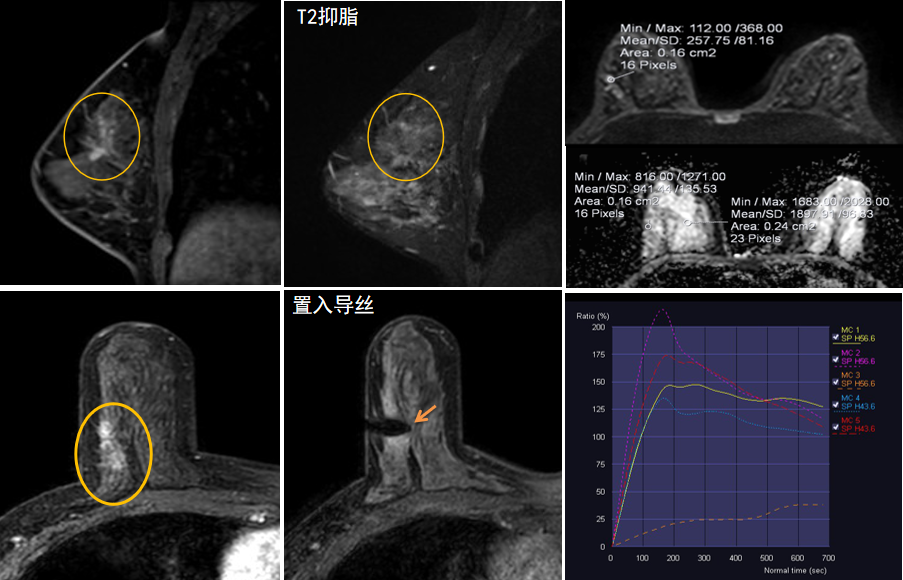

今年45歲的某女士,兩個(gè)月前行超聲檢查發(fā)現(xiàn)右乳結(jié)節(jié),乳腺X線攝影檢查提示右乳外上象限局部腺體結(jié)構(gòu)扭曲并簇狀無定形鈣化,為了進(jìn)一步評(píng)估病變性質(zhì)并確定范圍進(jìn)行了乳腺M(fèi)R平掃 DWI 增強(qiáng)的檢查,經(jīng)MR評(píng)估發(fā)現(xiàn)右乳病變范圍較廣,評(píng)估為BI-RADS 4類可疑病變,需要取得病理學(xué)結(jié)果。

西安國際醫(yī)學(xué)中心醫(yī)院影像診療中心陳寶瑩主任團(tuán)隊(duì)有著十余年影像引導(dǎo)下乳腺介入診療的經(jīng)驗(yàn),借助醫(yī)院高精尖的MR平臺(tái),成為西北首個(gè)全面展開MR引導(dǎo)下各項(xiàng)乳腺介入診療技術(shù)的團(tuán)隊(duì),能夠?qū)Τ暭叭橄賆線無法顯示或顯示不清的病變進(jìn)行MR引導(dǎo)下的導(dǎo)絲定位、穿刺活檢及真空輔助旋切。

陳寶瑩主任及其帶領(lǐng)的MR介入診療小組詳細(xì)詢問了病情,分析了患者資料,并與患者和臨床醫(yī)生進(jìn)行了充分溝通,確定于手術(shù)前為患者實(shí)施MR引導(dǎo)下的病變穿刺導(dǎo)絲定位和體表范圍確定。手術(shù)前陳寶瑩主任帶領(lǐng)聶品醫(yī)師、馬小偉技師、韓愛萍護(hù)士長等MR介入診療小組成員,借助MR高清的圖像顯示和定位系統(tǒng),確定病變范圍,精準(zhǔn)穿刺置入定位導(dǎo)絲,并準(zhǔn)確標(biāo)記出病變體表范圍,整個(gè)過程患者無任何不適。在定位導(dǎo)絲和體表范圍標(biāo)記的輔助下,甲乳外科劉曉敏主任精準(zhǔn)切除了病變,解除了患者的后顧之憂。

國內(nèi)外指南均建議40歲以上的女性每年行一次雙乳X線攝影(鉬靶)檢查,以篩查乳腺癌。對(duì)于乳腺癌高危人群40歲以前即建議開始乳腺癌篩查,除了進(jìn)行乳腺X線攝影(鉬靶)篩查外需要補(bǔ)充MR檢查,MR檢查敏感性最高,能夠發(fā)現(xiàn)大量X線攝影和超聲檢查陰性的可疑病變,基于多模態(tài)、多參數(shù)的結(jié)構(gòu)和功能成像的基礎(chǔ)上,MR能夠精準(zhǔn)顯示病變位置、范圍以及病變內(nèi)的活性區(qū)域,MR引導(dǎo)下的介入診療不但解決了僅在MR顯示的病變的處置難題,而且能夠精準(zhǔn)定位活性區(qū)域,保證了定位、活檢及旋切的準(zhǔn)確性。